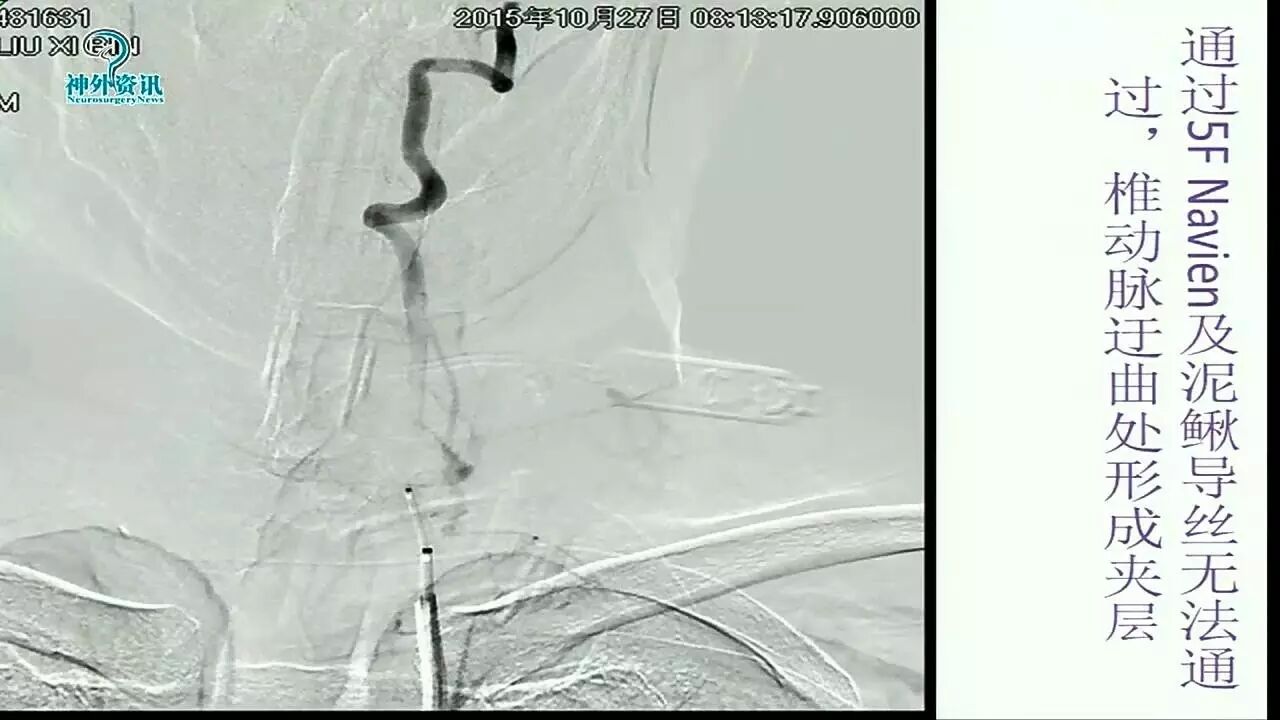

Enterprise支架在缺血性脑血管病中的应用